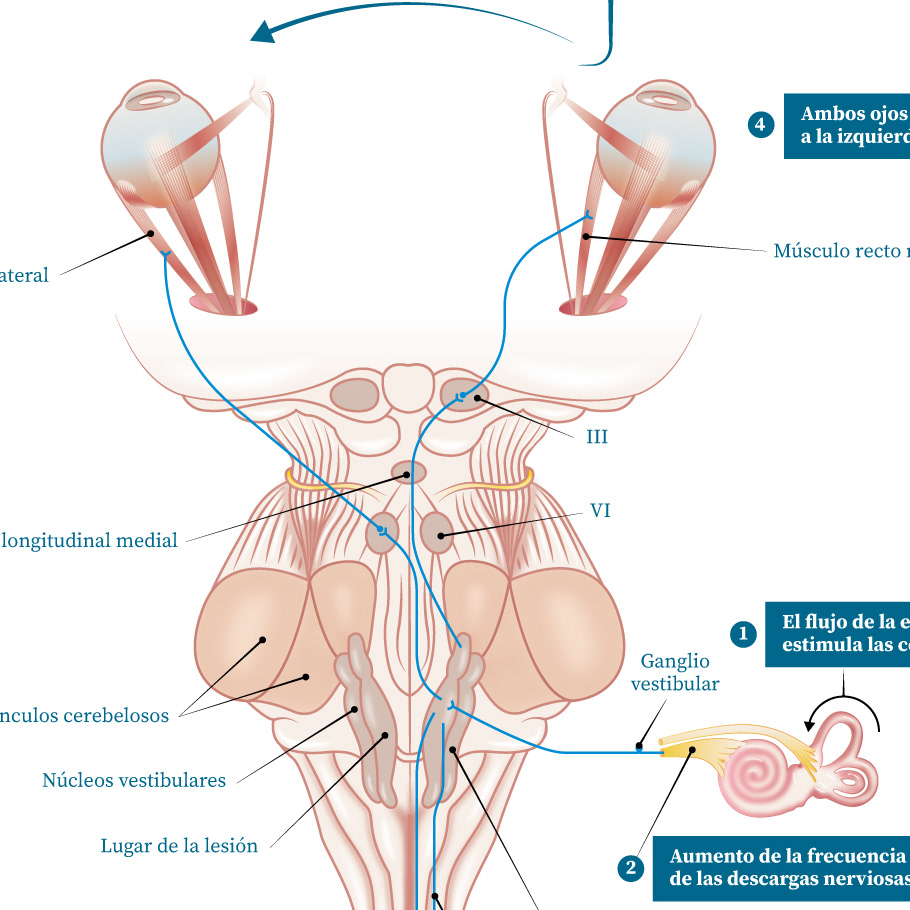

Ilustración Medica / Neurología

Neurología

Infografía / Otorrinolaringología